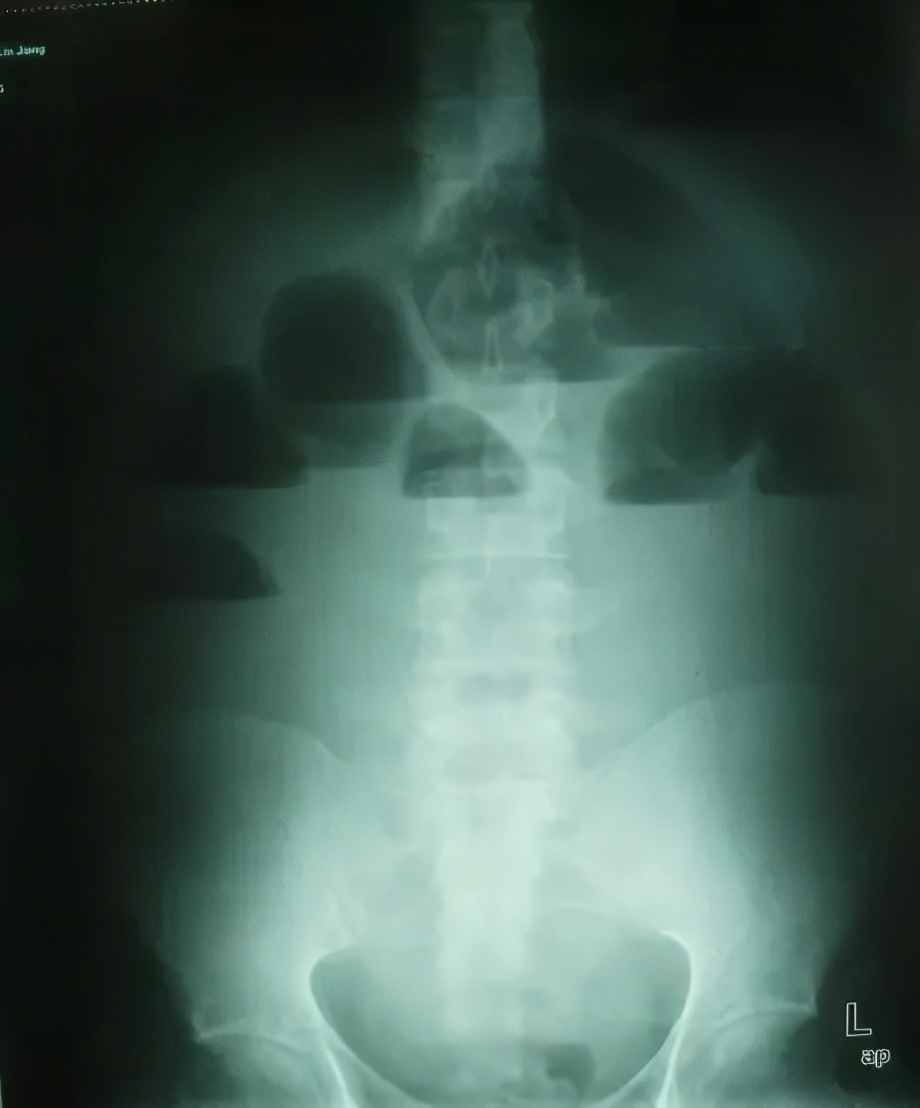

(1)立位或卧位腹平片: 肠梗阻4-6小时后即可检出肠袢胀气,表现为多个阶梯状气液平面;空肠粘膜的环状皱壁呈“鱼骨刺”样;绞窄性肠梗阻可见孤立、突出、胀大肠袢。 注意:X线阴性不能排除肠梗阻。怀疑肠套叠,肠扭转或结直肠癌时作钡灌肠。